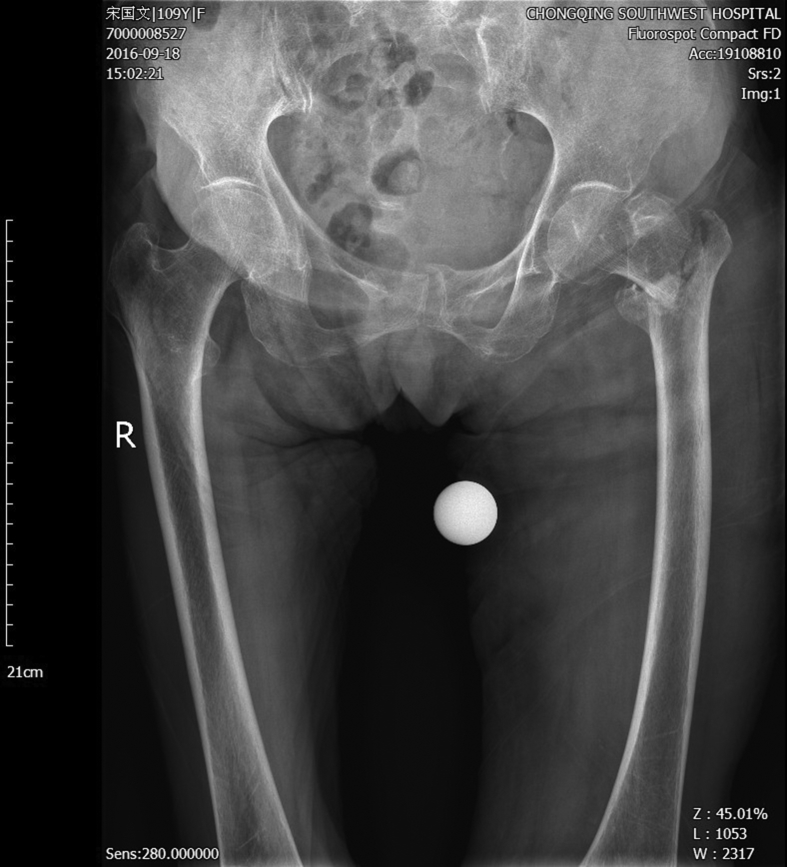

A 109-year-old female patient fell in the bathroom and could not stand up by herself with the left hip and the left palm injured. She was sent to a local hospital immediately. The X-ray examination showed left femur intertrochanteric fracture (Fig. 1). Due to the high risk of surgery of such super senior age, the operation was not performed. A week later, the patient was transferred to our department, and we found that she was in a good condition. She was able to walk indoor without crutches before the injury. Since there was no obvious surgery contraindication, the patient and his family decided to do the surgery hoping to restore the function and improve the quality of life. Physical examinations found ecchymosis in her left hip with the size of 8 cm × 20 cm, no skin damage and bedsore. With severe pain in the left hip, she prevented active activities from the left leg which resulted in shortening deformity. In April, she was hospitalized for one week for the pericardial effusion.

Fig. 1.

The preoperative X-ray shows intertrochanteric fractures without broken end shift.